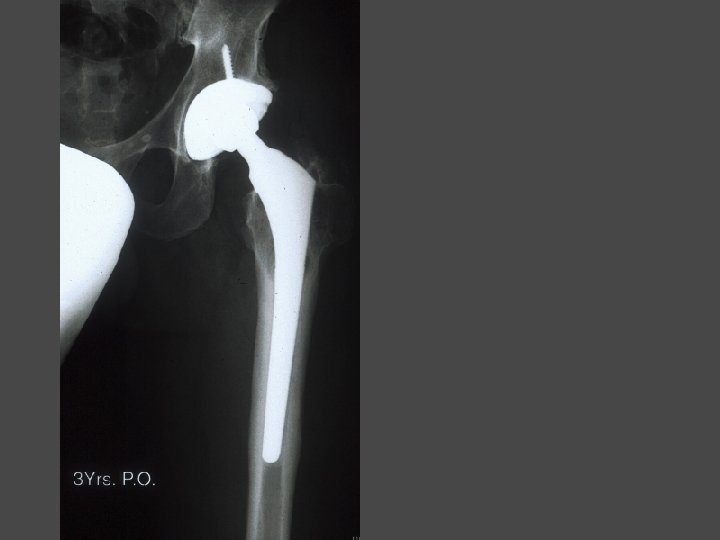

OSTEONECROSIS-THA Technical Considerations • Select implant using same criteria as for other Dx • Do not overream socket • Watch for socket fx • Augment socket fixation with screws • Choose femoral component depending on metaphyseal bone changes from previous surgery

OSTEONECROSIS-THA CONCLUSIONS • Final solution • Not a routine THA • At this time ? ’s remain about complications and durability • Future of AVN rests in avoiding collapse and thus avoiding THA